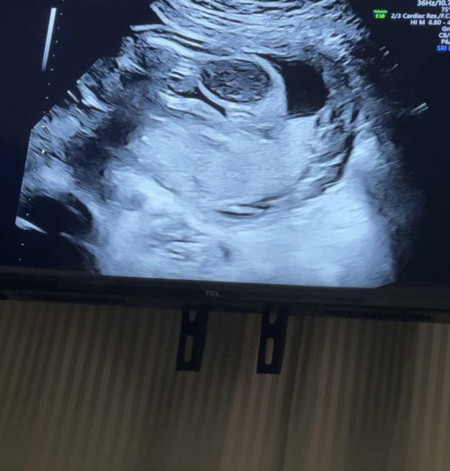

มีโอกาสจะได้เพศชายบ้างไหมคะ 23weeks ค่ะ

หมอบอกน้องเป็นผู้หญิงค่ะ แบบนี้มีโอกาสที่จะเป็นลูกชายบ้างไหมคะ🥺🙏🏻🤍 #ขอบคุณสำหรับคำตอบค่ะ

อาจจะยังไม่ชัดมาก ถ้าซาวด์อย่างเดียวอาจผิดพลาดได้นะคะ เห็นบางคนบอก ผญ ออกมาเป็น ผช ก็มีค่ะส่วนของเค้าตรวจเลือดถึงรู้ว่าเป็น ผช พอซาวด์ก็โชว์จุ๋ดจูเลย รอลุ้นชัดๆนะคะแม่

ตอน19วีคหมอที่โรงพยาบาลบอกว่าอาจจะได้ผู้ชาย.พอตอน21วีคไปซาวด์ที่คลีนิกข์หมอบอกว่าผู้หญิง100%ค่ะอ้าขาโชคจิมิไปเลยจ้า